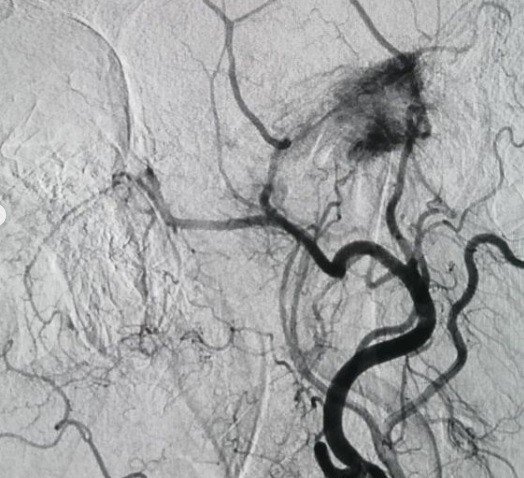

Bülent Ecevit Üniversitesi Uygulama ve Araştırma Merkezi Gelişimsel Radyoloji Doktor Öğretim Üyesi Yaşar Türk, Açıkçası hocamızın değerlendirdiği ve bizlere yönlendirdiği Glomus Tümörü ender görünen tümörlerden bu tümör bizim bölümümüzde doğru tanı koyulduktan sonra hocamızla konuştuk ve işlem öncesi embolisazyon dediğimiz damar yatağını kurutma işlemi yapılabilir mi diye konuştuk. Bunun için önce tanısal anjiyo yaptık. Bu vasküler tümörün bu tümörün yerini, nereden beslendiğini belirledikten sonra mikrobilyalar dediğimiz 300 mikron çapında tıkaçlarla bunları başka damarlara zarar vermeden bu tümörü devre dışı bıraktık. Hem hastamız hem de hocamız için bir konfor sağladık" şeklinde konuştu.